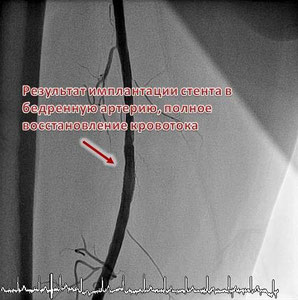

Стентирование артерий нижних конечностей

При сужении просвета сосудов нижних конечностей появляются трофические изменения, нарушения функции конечности (например, перемежающая хромота). Лечением этого заболевания является восстановление кровотока. Одной из операцией по восстановлению кровотока является стентирование артерий нижних конечностей. В нашем центра накоплен большой опыт выполнения стентирования артерий нижних конечностей. В своей работе мы используем инструменты и стенты последнего поколения и высочайшего качества. Это позволяет добиваться отличных результатов и быстрой реабилитации пациентов. Запись на консультацию - 8 (495) 201-68-33; 8 (499) 394-33-04.